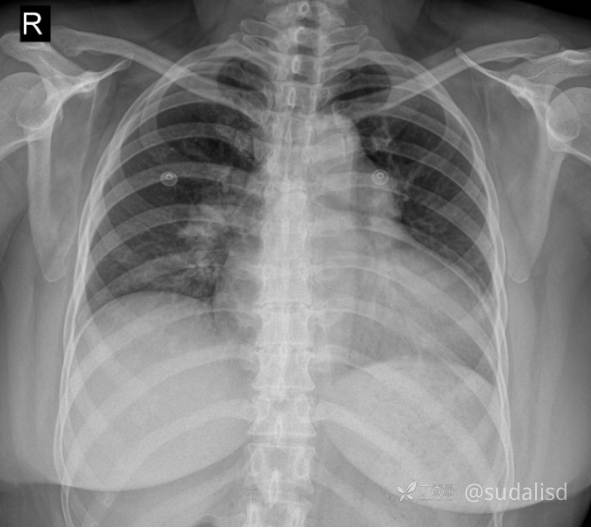

胸部X线如下图。